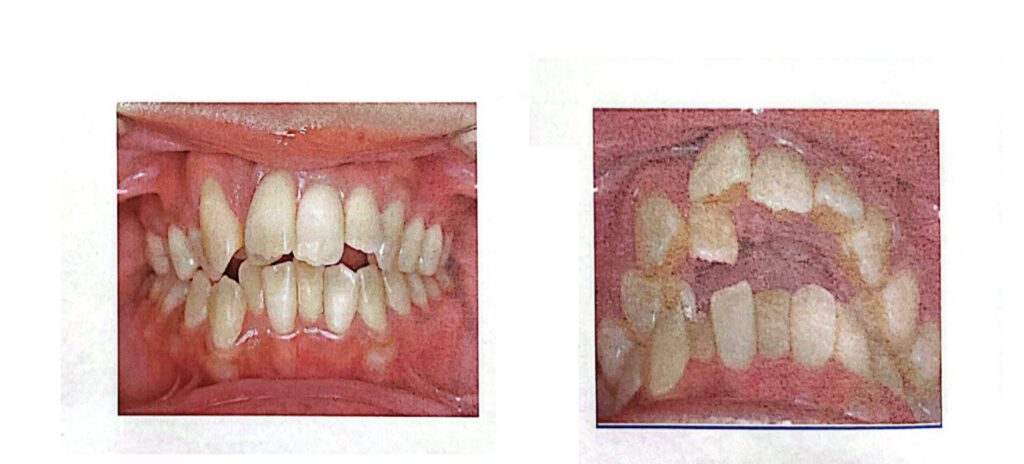

写真について

この後、参考として矯正前の歯並びの写真を掲載します。

苦手な方はここで終了していただければ幸いです。

↓現状の歯並びの写真です!

我ながらすごくガタガタですね…。前歯横の歯と前歯がほぼ重なっており、上下の前歯の間の噛み合わせのズレも大きいです。